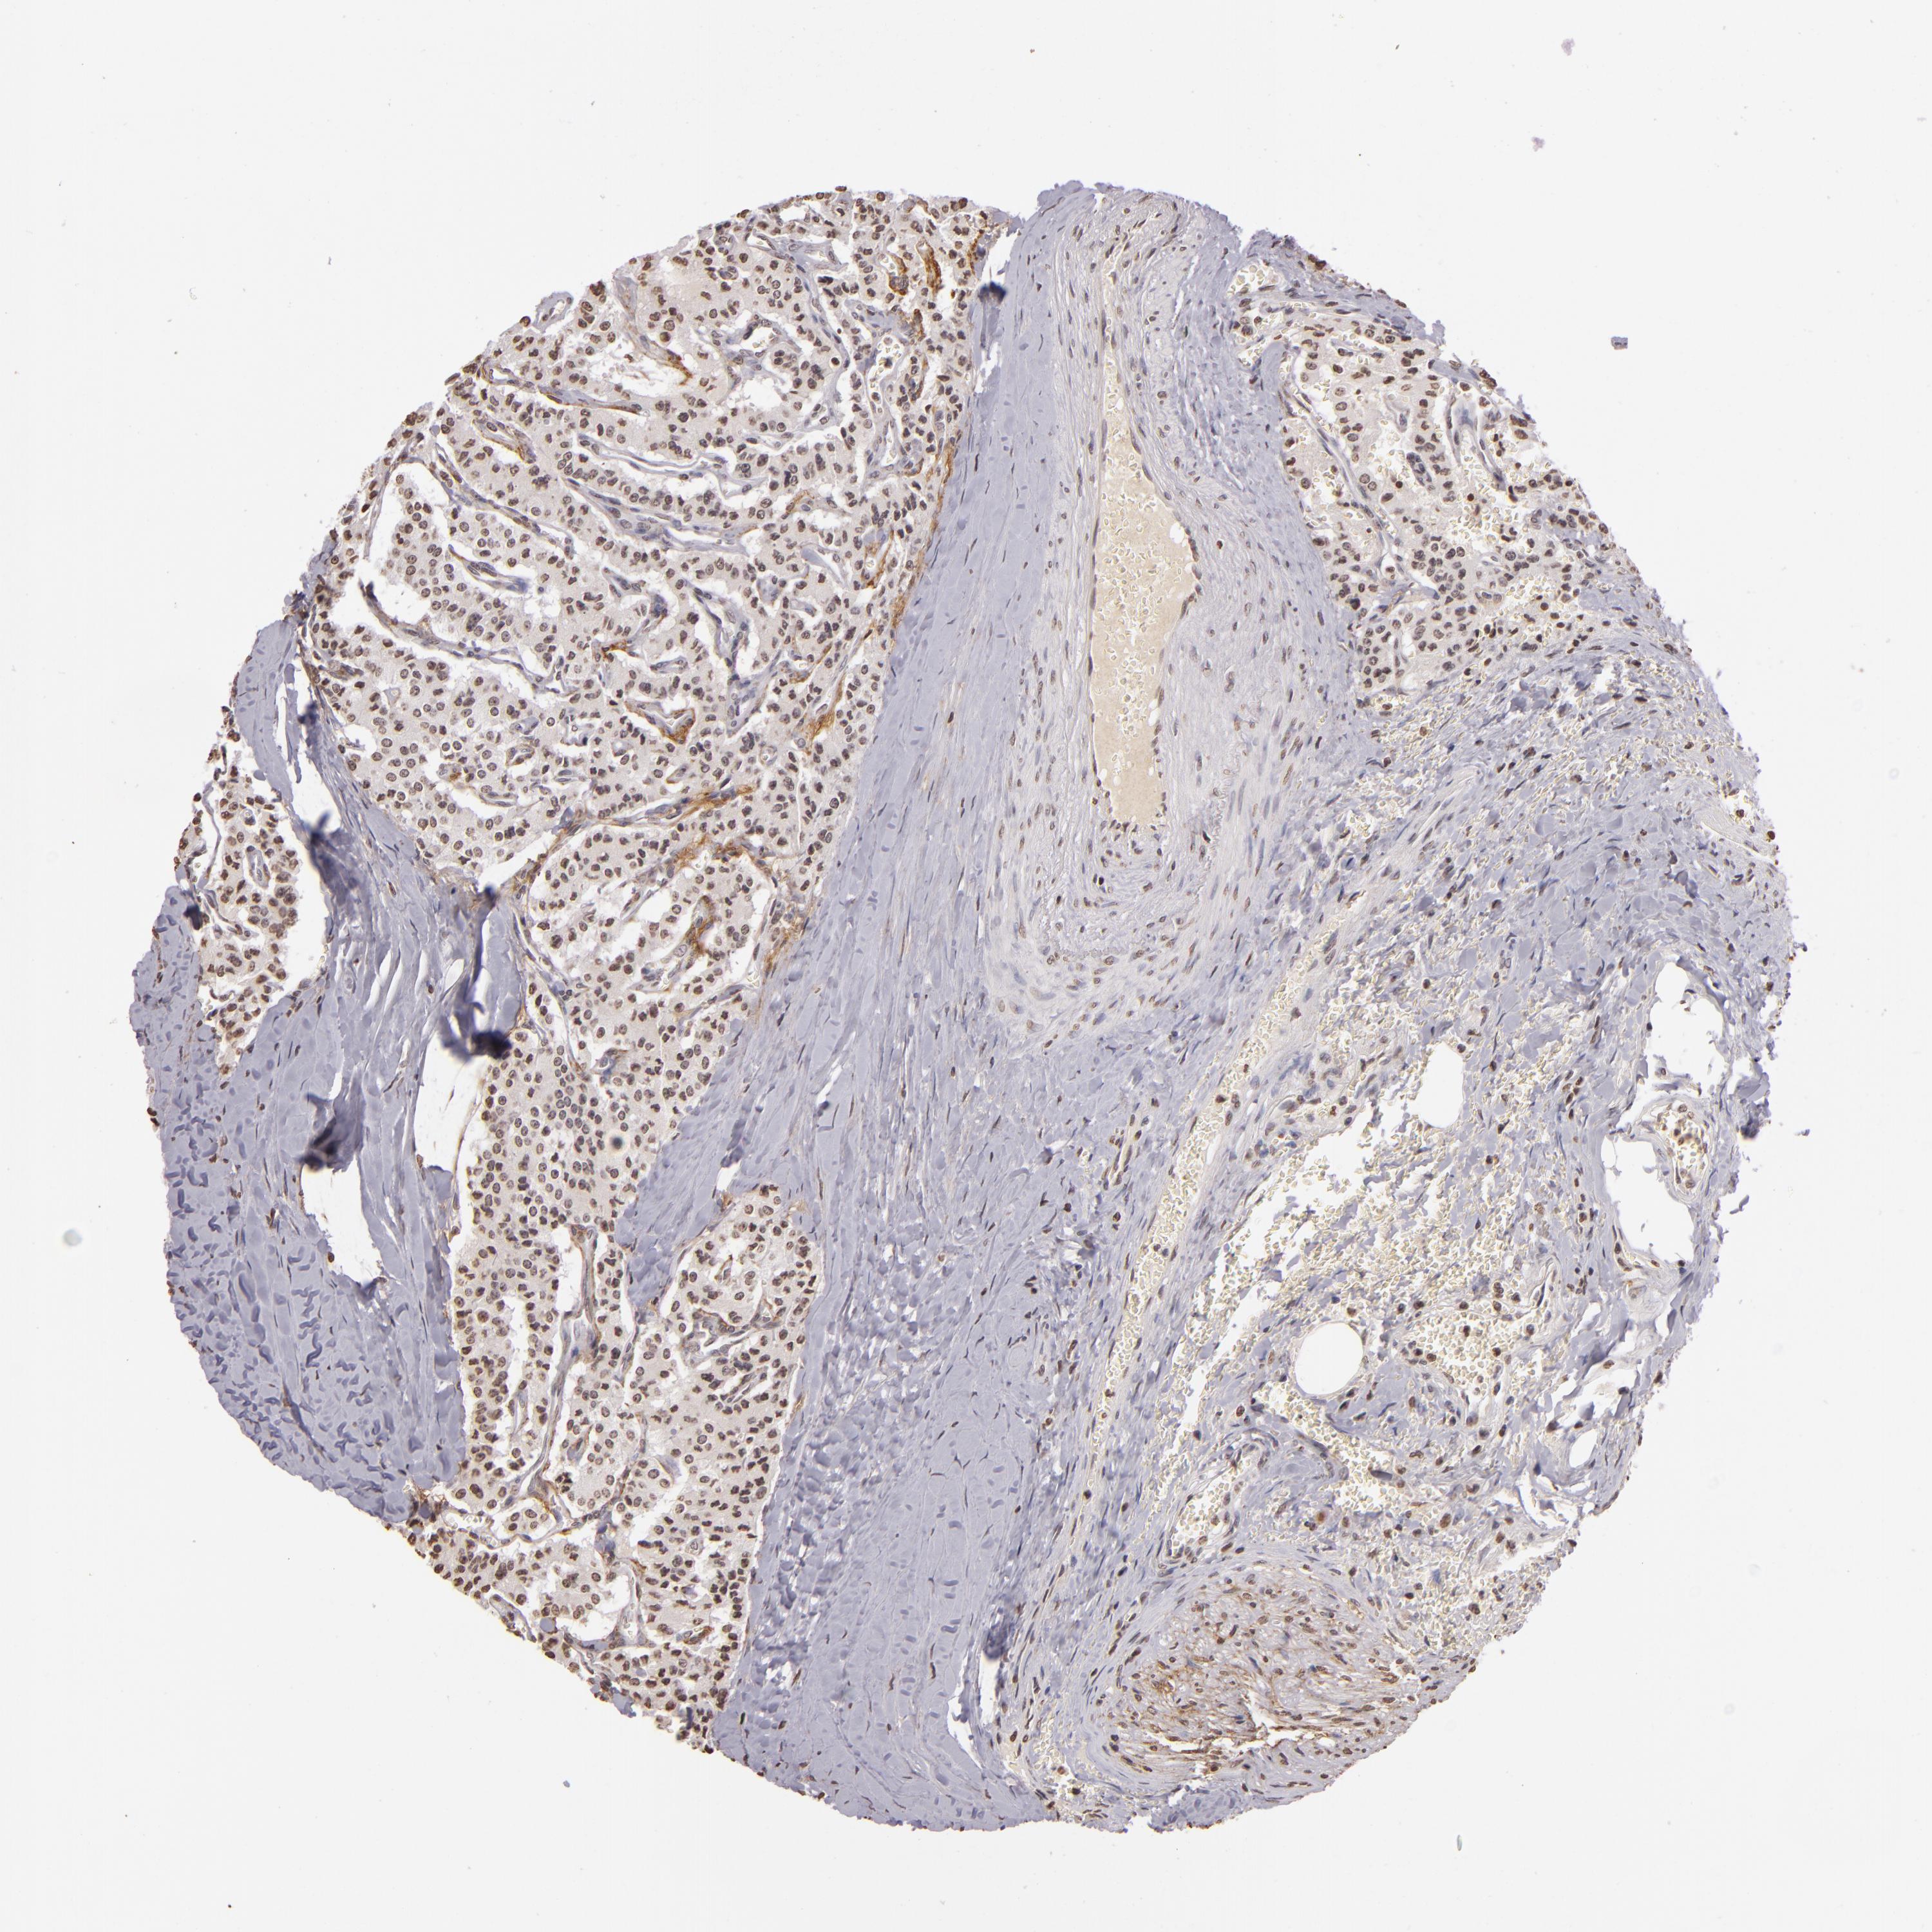

CARCINOID - Protein expressioni

A mouse-over function shows sample information and annotation data. Click on an image to view it in a full screen mode. Samples can be filtered based on level of antibody staining by selecting one or several of the following categories: high, medium, low and not detected. The assay and annotation is described here.

Note that samples used for immunohistochemistry by the Human Protein Atlas do not correspond to samples in the TCGA dataset.

Antibody stainingi

Antibody staining in the annotated cell types in the current human tissue is reported as not detected, low, medium, or high, based on conventional immunohistochemistry profiling in selected tissues. This score is based on the combination of the staining intensity and fraction of stained cells.

Each image is clickable and will lead to virtual microscopy that enables deeper exploration of all samples and also displays staining intensity scores, fraction scores and subcellular localization as well as patient and tissue information for each sample.

Antibody CAB002008

Antibody CAB002009

Staining

High

Medium

Low

Not detected

Intensity

Strong

Moderate

Weak

Negative

Quantity

>75%

75%-25%

<25%

None

Location

Nuclear

Cytoplasmic/membranous

Cytoplasmic/membranous,nuclear

Carcinoid, malignant, NOS